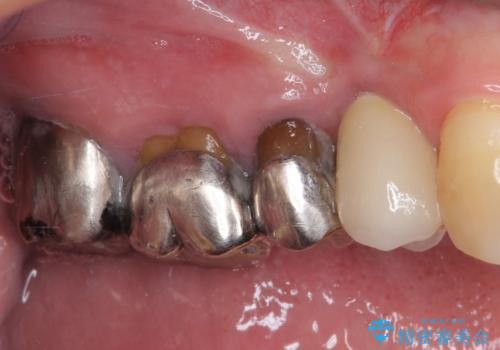

- 奥歯に違和感を感じており、抜歯の必要性を感じて来院された患者様です。

診査の結果、5本の奥歯を抜歯してインプラントによる補綴治療が必要と診断されました。

左上の奥歯は2本抜歯が必要であったため、治療期間中は右側に負担がかかり、頻繁に仮歯が壊れてしまいました。

左上に仮歯が装着されたからは咬み合わせが安定し、スムーズに治療を進めることができました。